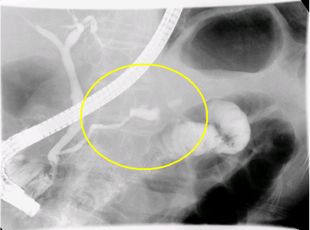

●ERCP(内視鏡的逆行性胆管膵管造影)検査

膵臓は十二指腸に接しており、膵管は十二指腸乳頭を通り、膵液という消化液を十二指腸に分泌しています。内視鏡を十二指腸まで挿入し、十二指腸乳頭から細い管を膵管の中に入れて、直接膵管を描出します。

膵臓がんによる膵管の圧迫を認めることがあります。また、膵液を採取して中にがん細胞がないかを調べます。

検査により膵炎を起こすことがあるため患者さんに負担のある検査ですが、膵臓がんの精密検査としては重要な検査です。

膵体部粘液性嚢胞腫瘍症例